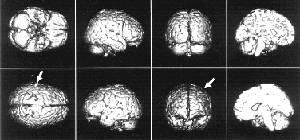

Интересные результаты дает такой эксперимент. Испытуемому рассказывают одновременно две разные истории: в левое ухо одну, в правое - другую. На фото1 изображены разные проекции мозга - стрелками отмечены активизированные зоны, когда внимание сосредоточено на истории, рассказываемой в левое ухо. Внимание испытуемого "переключилось" на "историю в правом ухе" (фото 2). Можно заметить, что для фиксации внимания на "историю в правом ухе" требуется гораздо меньшая активность мозга. Это связано с праворукостью большинства людей - обычно они берут телефонную трубку правой рукой и прикладывают ее к правому уху.

Исследования, проведенные в последние годы в Институте мозга человека Российской академии наук, позволили определить, какие области мозга отвечают за осмысление различных особенностей воспринимаемой человеком речи: за грамматику, синтаксис, орфографию и другие.

ОБЛАСТЬ, ОТВЕЧАЮЩАЯ ЗА ОПРЕДЕЛЕНИЕ ГРАММАТИЧЕСКИХ ХАРАКТЕРИСТИК СЛОВА

ЗОНА, АКТИВНАЯ ПРИ НЕОБХОДИМОСТИ ИСПОЛЬЗОВАНИЯ КРАТКОВРЕМЕННОЙ ПАМЯТИ

ЗОНЫ РЕЧЕВОЙ МОТОРИКИ

ЗОНЫ ПЕРВИЧНОЙ ОБРАБОТКИ ЦВЕТА

ЗОНЫ, УЧАСТВУЮЩИЕ В ОБРАБОТКЕ СИНТАКСИЧЕСКОЙ СТРУКТУРЫ ПРЕДЛОЖЕНИЙ

ЗОНА ОРФОГРАФИЧЕСКОЙ ОБРАБОТКИ СЛОВ

ОБЛАСТЬ, УЧАСТВУЮЩАЯ В СОЗНАТЕЛЬНОЙ И НЕПРОИЗВОЛЬНОЙ ОБРАБОТКЕ СМЫСЛА СЛОВ

ОБЛАСТИ, ПРЕДПОЛОЖИТЕЛЬНО УПРАВЛЯЮЩИЕ ПОДАВЛЕНИЕМ ОБРАБОТКИ РЕЧЕВЫХ ПРИЗНАКОВ В ЗАДАЧЕ НА ОБРАБОТКУ ФИЗИЧЕСКОГО ПРИЗНАКА СЛОВА, НАПРИМЕР ЦВЕТА